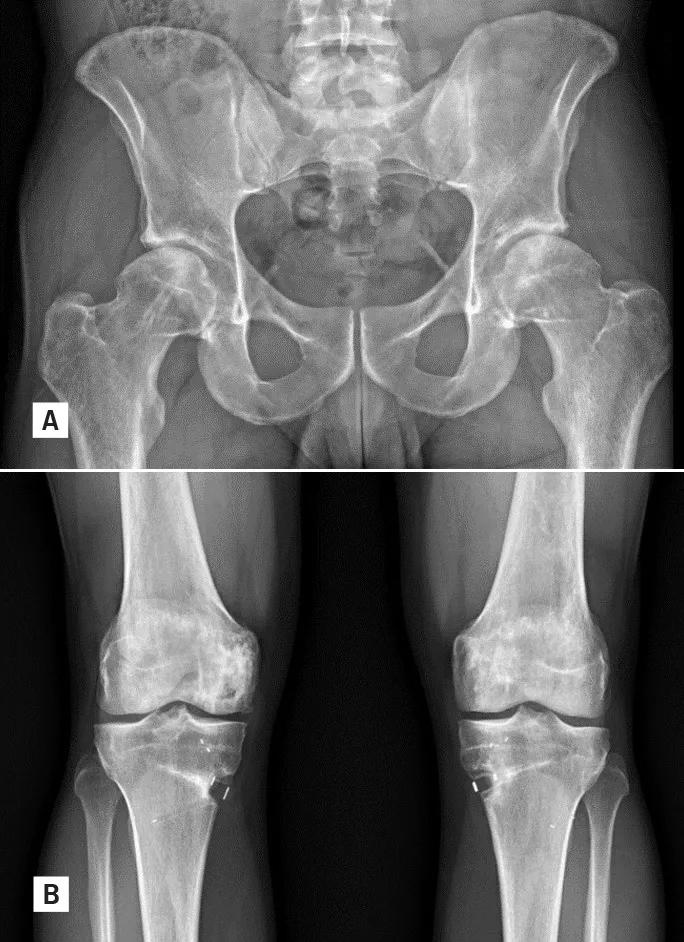

The patient recovered remarkably well. Post-operative imaging demonstrated satisfactory healing and maintained limb alignment (Figures 3A & B). As soon as he completed his dedicated post-operative physical rehabilitation protocol after his most recent knee surgery, he began working with a personal trainer to prepare for an Ironman event, which he would go on to complete less than one year later.

Figure 3. Postoperative anteroposterior pelvis (3A) and bilateral knee (3B) radiographs.